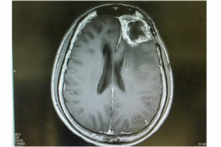

Một phát hiện từ Đại học Tel Aviv đã tiết lộ một phương pháp đáng chú ý mới có thể khiến một loại khối u não có sức tàn phá mạnh mẽ – u nguyên bào thần kinh đệm – bị ‘bỏ đói’.

Theo các nhà nghiên cứu, u nguyên bào thần kinh đệm là một căn bệnh ung thư não gây chết người và không có phương pháp điều trị hiệu quả. Họ viết: “Các tế bào khối u có khả năng chống lại tất cả các liệu pháp đã biết, và đáng buồn là tuổi thọ của người bệnh không tăng đáng kể trong 50 năm qua.”